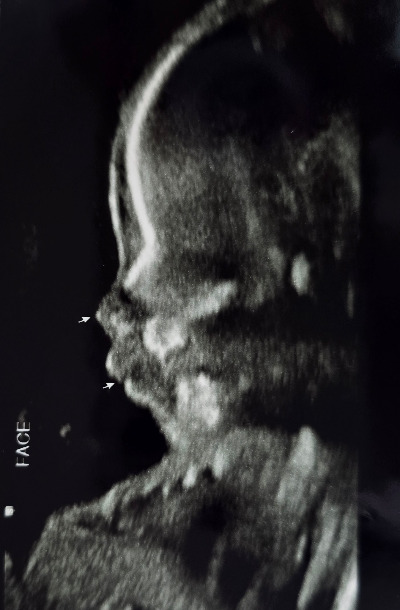

임신 중반을 지나면서 아내의 배가 점점 불러왔다. 여전히 입덧이 있었지만 초기보다는 많이 나아져서 먹을 수 있는 음식도 많이 늘어났다. 계속 줄어들기만 하던 몸무게도 양수와 둥글이의 영향인지 다시 늘기 시작했다. 27주 차에 두 번째 입체초음파 검사를 하였다. 입체 초음파 검사는 일반 초음파와 달리 아이의 형상을 3D 입체 영상으로 확인할 수 있는 검사다. 이미 12주 차 첫 번째 입체초음파 검사를 했었는데, 이때는 둥글이의 머리통과 팔다리 형상만 겨우 구분할 수 있었다. 그런데 두 번째 입체초음파 검사는 달랐다. 우리 부부는 이날 둥글이의 얼굴을 처음으로 선명하게 보았다.

1-10.jpg

1-11.jpg

12주 차와 27주 차의 입체 초음파 사진. 한 화면에 들어오지 않을 만큼 컸다.

어느새 쑥쑥 자라 한 화면에 담을 수도 없는 둥글이는 슬며시 얼굴 반쪽을 내보여 주었다. 감고 있는 눈과 작은 코, 심통 난 듯 불퉁한 볼과 입까지... 마치 아이를 눈앞에 두고 있는 듯 생생한 모습이었다.